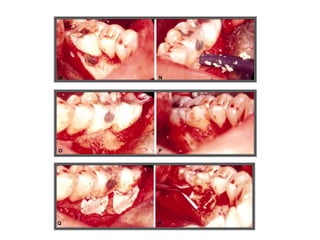

TRATAMENTO DAS LESÕES

ENDOPERIODONTAIS

Rizectomia

DEL RIO, 1996

Rizectomia

Hemisseccção